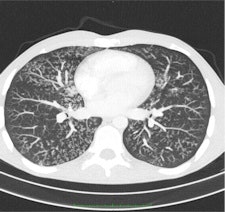

CT is now used as a diagnostic tool in a number of chest diseases, particularly in lung cancer, pulmonary embolism, interstitial lung diseases, and even to diagnose complications in pneumonia. In the diagnosis of interstitial lung diseases in particular, CT is particularly useful because the pathologic changes in such diseases may be very subtle, necessitating a CT with very thin sections.

A number of potential protocols can be used to evaluate interstitial lung diseases with CT. The two main methods are discontinuous HRCT using 1-mm-thick slices with an intersection gap of 10 to 20 mm and volume CT. Compared with volume CT scans, discontinuous HRCT scans show only 10% of all information.